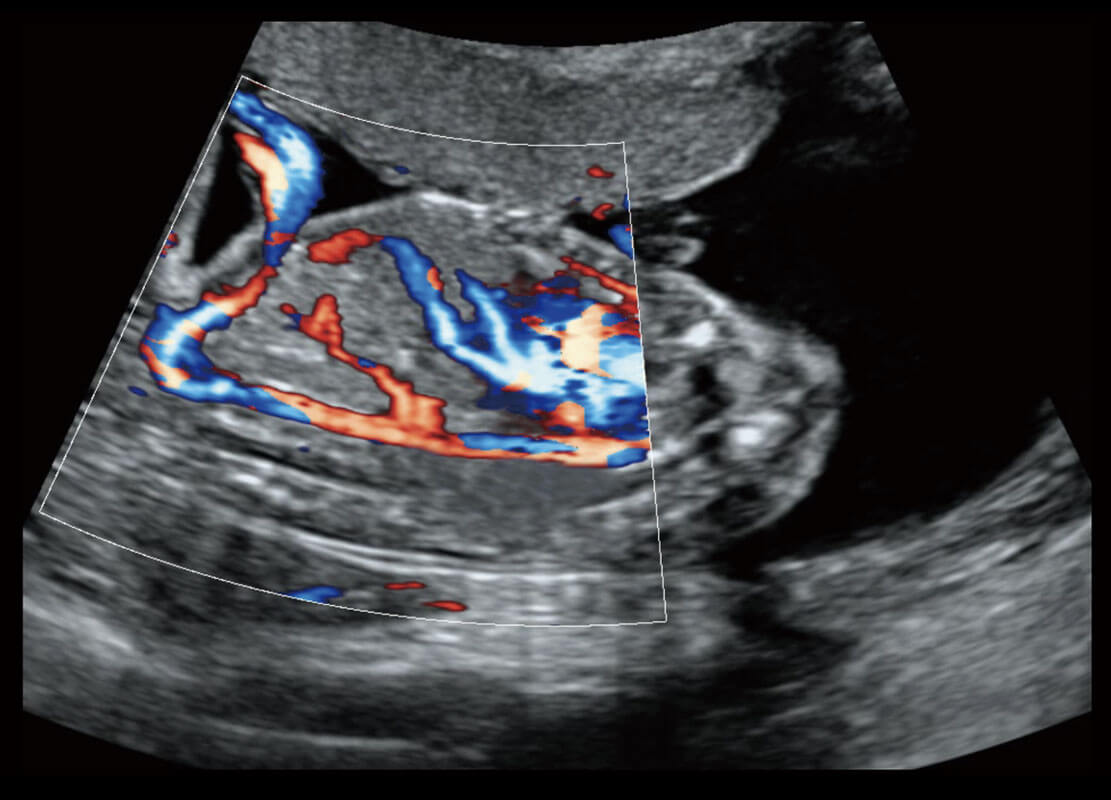

P60搭载一系列胎儿心脏成像技术,实现精细的胎儿心脏评估。

四腔心血流

胎心容积成像